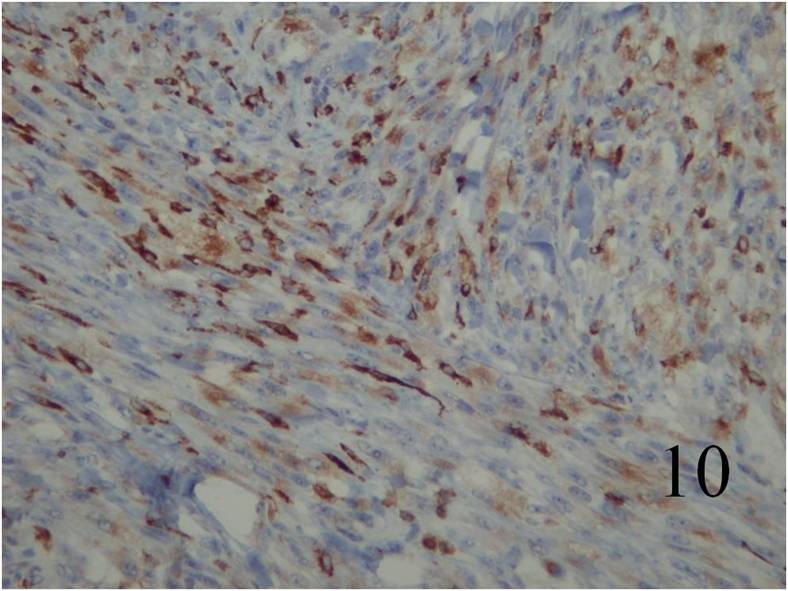

Fig. 7 Microscopic: Low and High (Fig. 8) power magnification of a leiomyosarcoma showing palisading spindle cells; with eosinophilic cytoplasm. Immunohistochemical stains for leiomyosarcoma are positive stain for actin (Fig. 9) and desmin (Fig. 10)

Desmin and Actin are positive (Fig. 9,10 – above)